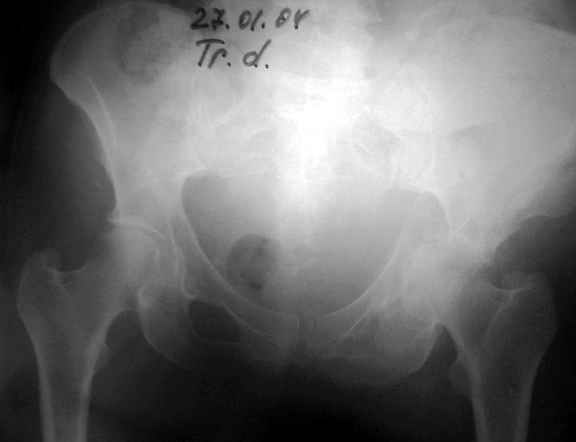

27.01.04